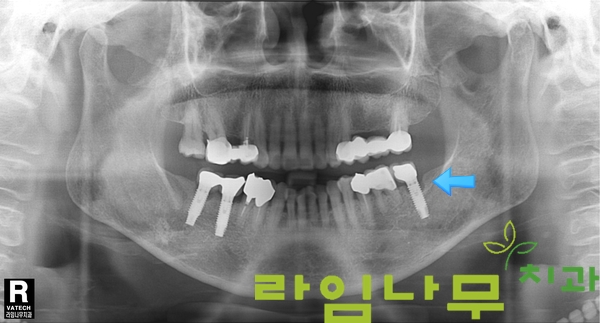

타치과에서 수술받았던 왼쪽 아래 어금니 임플란트가 불편하시다는 주소로 라임나무치과에 방문해주신 환자분이신데요,

X-ray를 촬영하여 판독한 결과, 화살표 표시된 임플란트 주변부에 하얗게 차 있어야 할 잇몸뼈가 까맣고 동그란 모양으로 내려간 것이 보이시나요?

임플란트 주위염으로 인하여 임플란트 주변 뼈가 녹고 있음이 확인되었습니다.

이러한 경우 잇몸 뼈가 내려가면서 임플란트 보철과 잇몸 사이로 음식물이 많이 끼이기도 하고, 흔들리는 듯한 증상이 나타나게 되죠.

위 환자분은 임플란트를 제거한 후 즉시 소실된 뼈가 다시 차오를 수 있도록 인공 뼈 이식을 진행, 임플란트를 재식립하는 임플란트 재수술이 시행되었습니다.